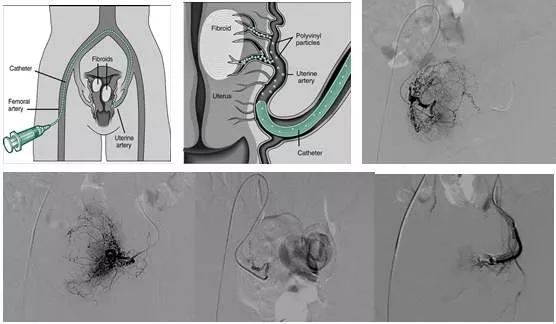

子宫肌瘤介入治疗原理

在腹股沟韧带中点下0.5厘米处触及股动脉博动最强处作为穿刺点,经导管推注一定大小,一定量的栓塞颗粒将子宫肌瘤供血血管及正常子宫动脉分支的一定末梢血管栓塞。

介入栓塞术的治疗原理:

(1)可以直接切断子宫肌瘤的血液供应,瘤体缺血坏死,逐渐萎缩变小,并改善由于肌瘤占位所引起的压迫症状。

(2)子宫肌瘤具有性激素依赖性,雌激素能促进肌瘤生长。切断肌瘤供血能阻雌激素经血流进入肌瘤内,瘤体雌激素水平显著下降,局部形成一个类似绝经期的激素内环境,肌瘤进一步萎缩。

(3)子宫动脉栓塞后,子宫血供显著下降,子宫内膜生长受到抑制月经量减少,经期恢复正常。贫血逐渐得到改善和恢复。